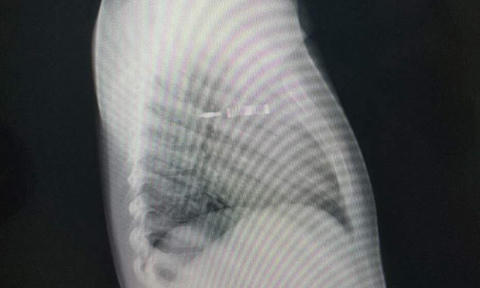

Các bác sĩ nhanh chóng đã chụp X-quang, CT, kết quả cho thấy cây bút đâm gần lút cán, rách màng phổi, mũi bút nằm ngay giữa trung thất ở trung tâm lồng ngực, vừa xuyên thủng tĩnh mạch chủ trên, nhưng may mắn chưa gây vỡ tĩnh mạch chủ. Ngay lập tức, bệnh nhi đã được mổ cấp cứu, lấy cây bút ra.